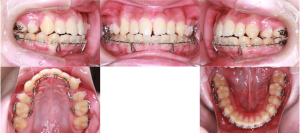

※矯正治療開始時

治療を進めやすくするために、噛み合わせを一時的に少し高くした状態で矯正治療を開始しました。

上の歯には装置が目立ちにくい舌側(内側)に、下の歯には一般的な唇側(外側)に装置を装着する、いわゆるハーフリンガル矯正を行いました。

この方法は、矯正治療中に装置の見た目が気になる方に配慮した治療方法の一つです。

※矯正治療中の正面

上記の写真のように、ハーフリンガル矯正では、上の歯は内側に装置を装着するため、見た目には装置が付いていないように見えることがあります。